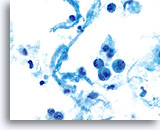

Polymorphonuclear cells may be engulfed in the cytoplasm. 60x

Tumor diathesis and single malignant cells may be noted. 60x